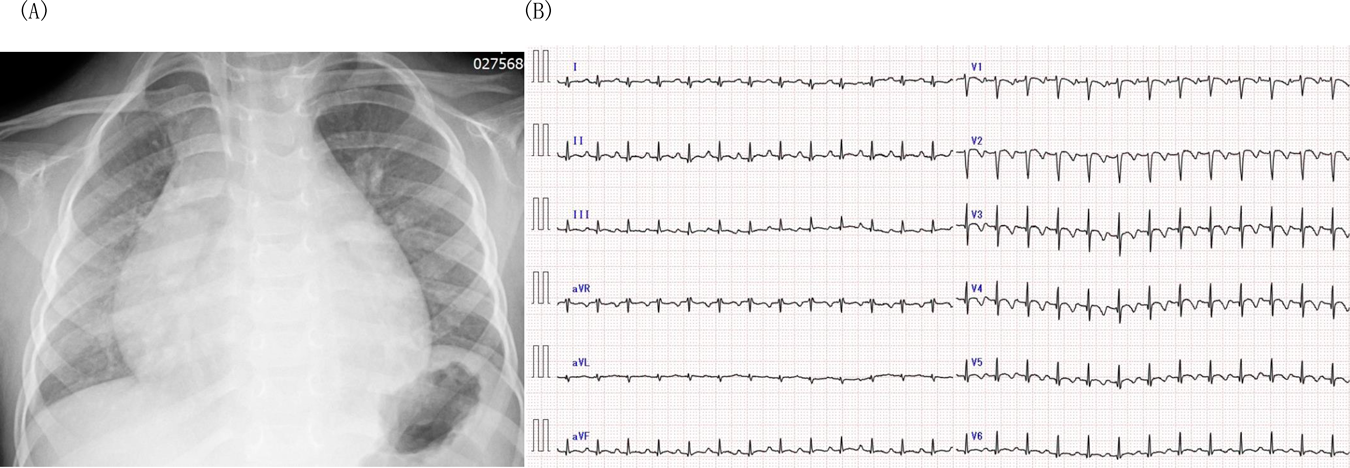

来院時の経胸壁心臓超音波(Fig. 3)で,両心収縮機能低下と軽度心嚢液貯留を認め,特に心尖部の心収縮性低下が著しかった.急性心筋炎を疑いガンマグロブリン(以下IVIG)(2 g/kg)単回投与とプレドニゾロン(以下PSL)(2 mg/kg/日)投与を開始し,心不全治療としてフロセミド(1 mg/kg/日),スピロノラクトン(1 mg/kg/日),ミルリノン0.4γを投与した.第7病日より後負荷の軽減と心筋線維化の予防のためエナラプリルマレイン酸を0.05 mg/kg/日より開始し,0.2 mg/kg/日まで漸増した.ミルリノンは第27病日で投与終了とした.血液検査で心筋逸脱酵素が低下したためPSLを漸減し,第7病日に中止した.その後末梢血中の好酸球分画が第9病日:5%(WBC 10,600, 530/µL),第11病日:13%(WBC 10,600, 1,380/µL)と上昇し,CK, CK-MB, AST, Troponin値も上昇した.EMCを強く疑い,第11病日よりPSL(2 mg/kg/日)投与を再開した.同日の経胸壁心臓超音波(Fig. 4)で右室心尖部に巨大血栓を認めたため,ヘパリン静脈内持続投与に加え,ワルファリン(0.1 mg/kg/日)の内服も開始した.第13病日には血栓は消失し,胸部CTで肺動脈内にも血栓はなかったため,第16病日にヘパリン持続投与を中止し,アスピリンの内服を追加した.第20病日よりPSLを内服に切り替え,第34病日より漸減開始した.好酸球数,CK, CK-MB, AST, Troponin Tの推移を確認しながらPSLを6 mg/日(0.4 mg/kg/日)まで減量した.減量後に心機能の悪化や筋逸脱酵素の上昇はなく経過したため第81病日に退院した.退院後3日より左眼の焦点が合わず,退院後7日に近医眼科を受診し,左眼外斜視と診断された.他の外眼筋麻痺はなかった.退院後9日より歩行困難となり,退院後11日に近医を再診した.左外斜視に加え,右上眼瞼下垂を認め,MGが疑われたため退院後17日に入院した.左眼球斜視,右上眼瞼の軽度下垂,動揺性歩行とGowers徴候を認めた.エドロホニウム試験で眼瞼下垂が改善し,反復刺激試験でWaningが再現性を持って確認され,全身型MGと診断された.胸部CT,非造影MRIでは胸腺腫はなく,骨盤~下肢骨格筋MRIでも筋炎を疑う所見はなかった.自己抗体に関しては抗アセチルコリン(AChR)抗体,抗Musk抗体,抗横紋筋抗体は陰性,筋炎特異的自己抗体としてJo-1,ARS,MDA5,Mi-2,TIF-γ,ミトコンドリアM2抗体も全て陰性であった.PSL(2 mg/kg/日)の隔日投与,IVIG(400 mg/kg/日)の5日間投与に加え,タクロリムスを開始し,症状が改善したため退院した.その後も近医にて加療中でMGの治療経過中に心筋炎の再燃はなかった.

Fig. 4 Thrombus attached to the apex of right ventricle